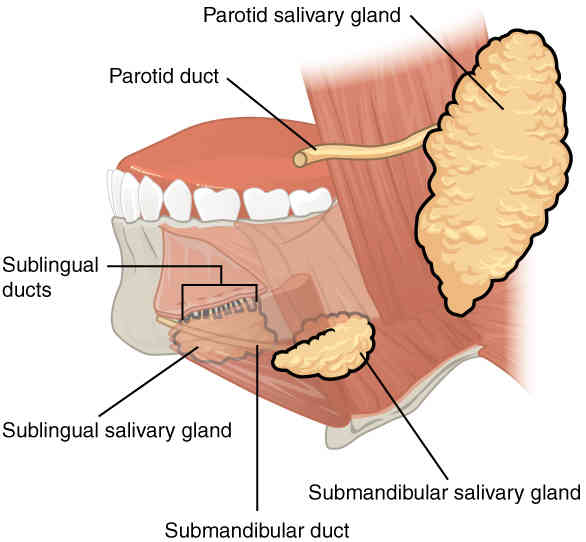

This page is under construction. For now, it is just a resource of the images found in the OpenStax Anatomy and Physiology Handbook. It wil slowly change into a revision tool. Each slide has a number. Use this to refer to the slide. When completed, it will have an unlabelled section, with labelled slides in parallel. On the unlabelled slides, write your answer and use the labelled slide to assess yourself. Keep track by also noting the number on each slide. Improvement at each attempt is important, more so than full marks on a first attempt.